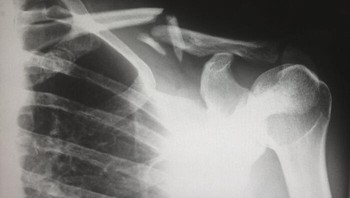

Ketika teknologi sinar-X pertama kali tersedia secara luas untuk dokter anak, mereka melihat sejumlah besar patah tulang yang mengejutkan. Ternyata terungkap banyak anak yang mengalami pelecehan dan kekerasan. Foto: Reddit via Bored Panda